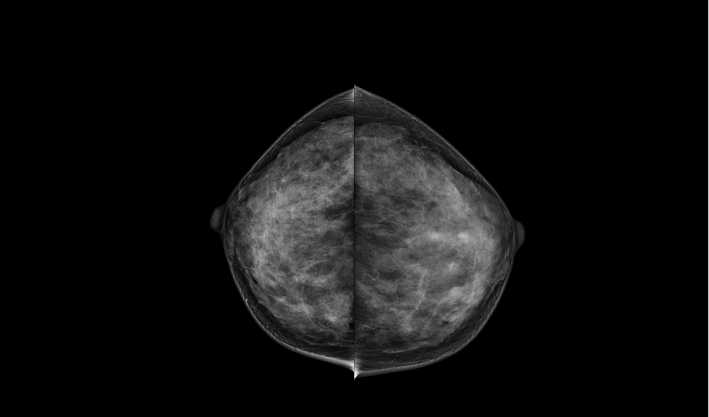

頭尾位(CC位) 內外斜位(MLO位) 補充體位(根據需求)

一鍵式視圖切換

致力于致密乳腺的早期癌變篩查和微鈣化簇精準定性。